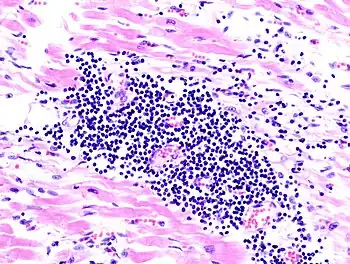

- Histopathologic examination